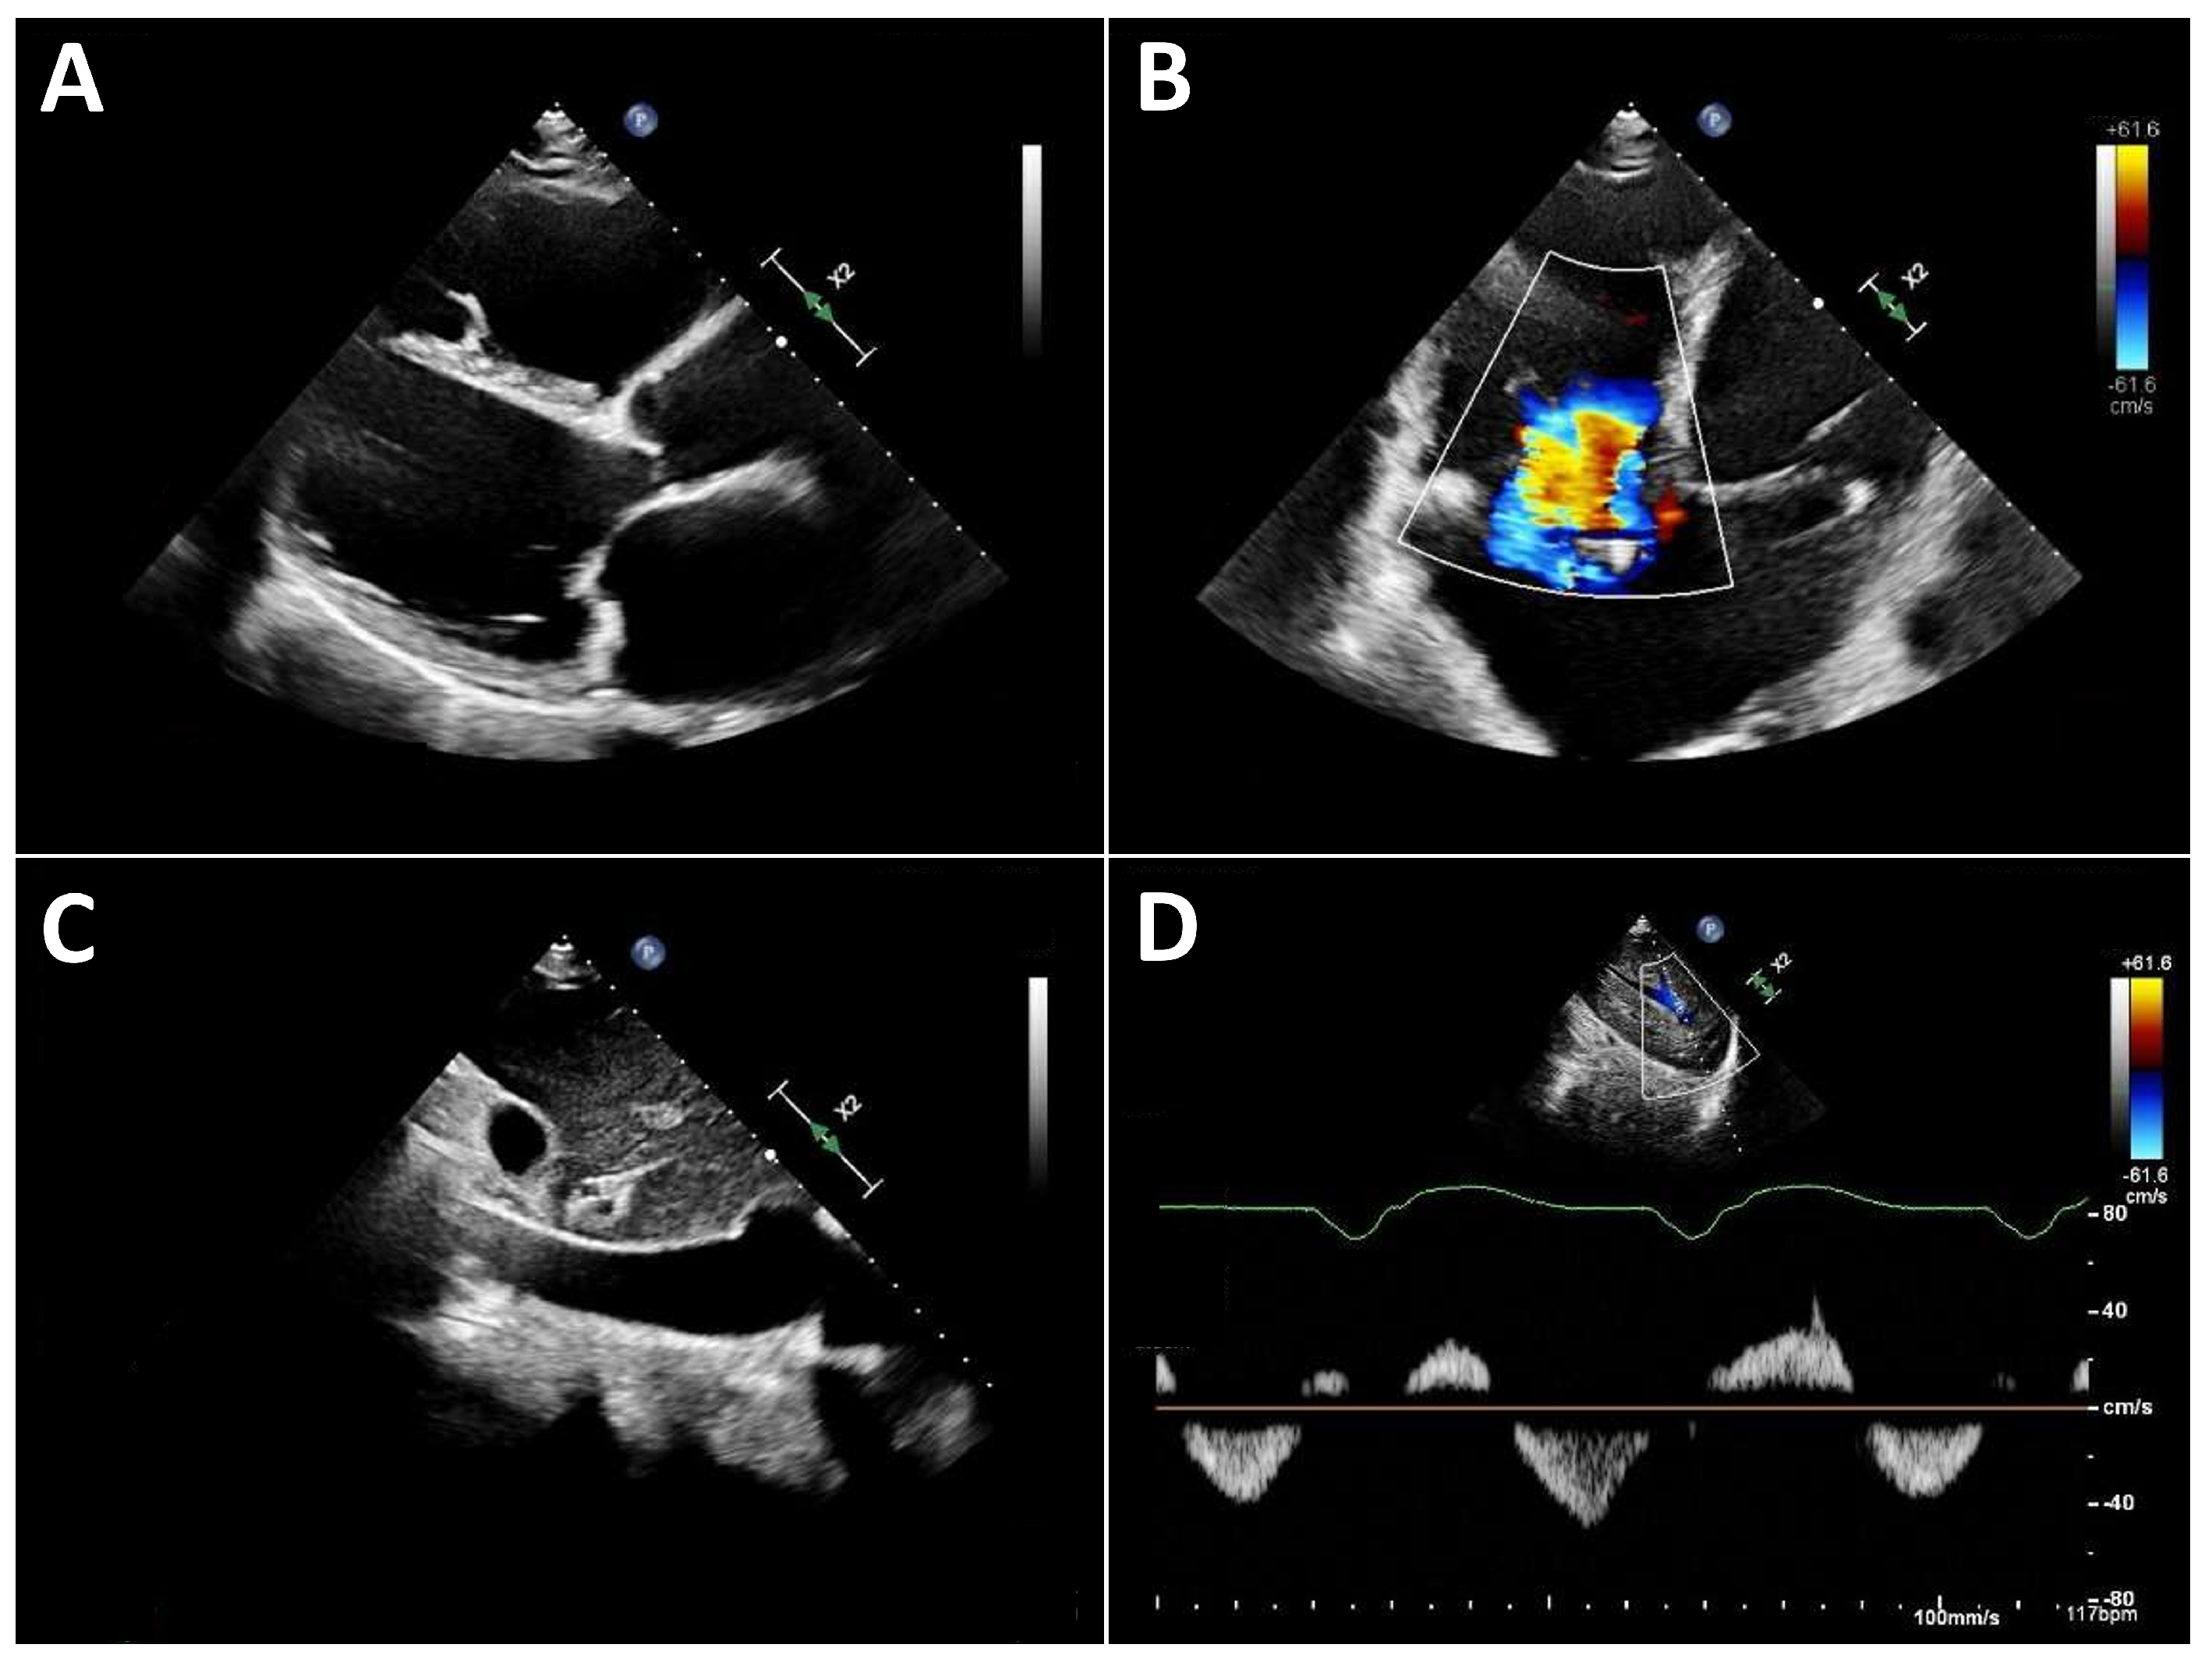

Typical echocardiographic signs of right ventricular failure include right ventricular dilatation, reflected by an increase in the proximal RV outflow tract (RVOT) diameter and RVD1 (Figure 3). This is frequently accompanied by dilatation of the tricuspid annulus with progressive tricuspid regurgitation. In severe cases, a leftward deviation in the interventricular septum may be observed. In advanced stages, the inferior vena cava is markedly dilated and exhibits significantly reduced respiratory variation. Quantification of tricuspid regurgitation can be performed using the standard guideline-recommended parameters, with a five-grade severity classification that has proven useful [31].

Figure 3.

Typical echocardiographic findings of severe right heart failure in a patient with LVAD support. (A): Parasternal long-axis view showing a markedly dilated and hypokinetic proximal RVOT. (B): Apical view demonstrating pronounced right ventricular dilatation and severe tricuspid regurgitation. (C): Markedly dilated inferior vena cava with severely reduced respiratory variation. (D): Systolic flow reversal in the hepatic veins.